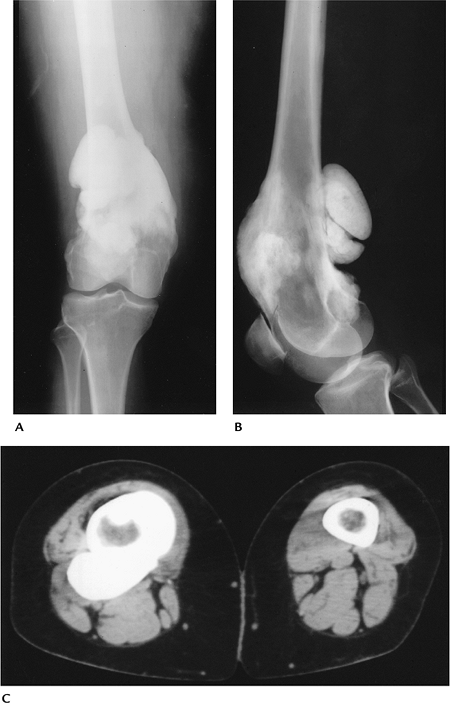

Bone Tumors/Tumorlike Conditions: Parosteal Osteosarcoma

Patients typically present with a painless mass in the distal posterior thigh.

-

Age: Third decade (older than conventional osteosarcoma)

Sex: Females outnumber males 2:1.

Common locations: majority in distal posterior femur (67%), proximal tibia or fibula (12%), proximal humerus (10%)

Imaging features:

Radiographic features: large ossified

mass on the surface of a long bone. Cortex thick and deformed. Larger

masses may surround bone. -

CT: similar to radiographs. Lucent zone (periosteum) separates the tumor from the cortex (string sign).

MRI: often not required because of characteristic CT features and lack of improved specificity for MRI.

Differential diagnosis:

Myositis ossificans

Periosteal osteosarcoma

Osteosarcoma

Periosteal chondrosarcoma

Treatment: limb salvage resection

P.680

![]() |

|

FIGURE 10-26 Parosteal osteogenic sarcoma. AP (A) and lateral (B) radiographs showing dense osseous mass surrounding the lower femur. (C) CT image showing the dense osseous mass around the femur.